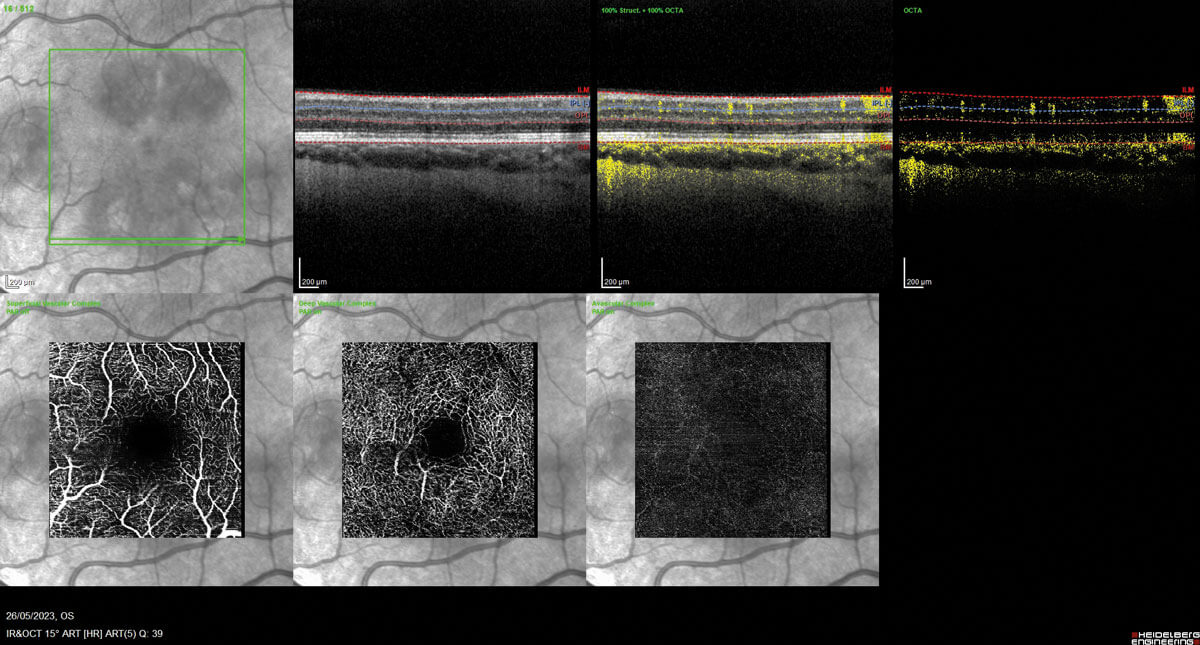

Figures 2a and 2b: OCT angiography left eye (2a - top) and right eye (2b - bottom).

Fundoscopy showed evidence of discrete foveal reflex changes, which on further evaluation with optical coherence tomography (OCT) macular view showed multiple areas of outer retinal disruption (see Figures 1a and 1b). Optical coherence tomography angiography displayed evidence of reduced flow in the deep retinal plexus, consistent with ischaemia (Figures 2a and 2b). These retinal imaging findings correlated with the patient’s subjective visual changes, as noted on their Amsler grid drawings (see Figures 3a and 3b).